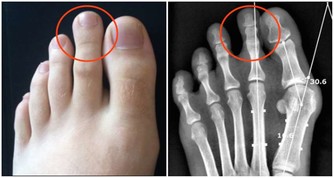

每日服用1克維生素C易發生腹瀉,一次服4克會導致尿酸尿,長期大劑量服用會使一些病人形成尿道草酸鹽結石,並使6—磷酸葡萄糖脫氫酶(G—6-- PD)缺乏症病人出現溶血。